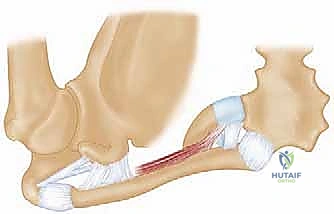

Modern stabilization relies on robust biological reconstruction. While primary repair of the capsule using suture anchors in the manubrium can augment the construct, a figure-of-eight graft reconstruction is the gold standard for restoring multiplanar stability. A semitendinosus or gracilis autograft (or allograft to minimize donor site morbidity) is preferred due to its length and tensile strength.

The graft is then passed in a figure-of-eight configuration. Suture passing wires or curved shuttles are used to navigate the graft through the osseous tunnels. The graft is tensioned with the clavicle held in anatomical reduction (often requiring downward and posterior pressure on the medial clavicle). The graft limbs are then sutured to themselves and to the surrounding periosteal tissues using heavy, non-absorbable, braided sutures.

In cases of recalcitrant recurrent instability, deep infection necessitating graft removal, or severe post-traumatic osteoarthritis of the SC joint, salvage procedures must be considered. The primary salvage operation is an excision of the medial clavicle. However, this is not a simple resection. The excision must be meticulously planned to remove no more than 1.5 to 2.0 cm of the medial clavicle. Crucially, the insertion of the costoclavicular (rhomboid) ligament on the inferior aspect of the clavicle must be absolutely preserved. If the costoclavicular ligament is violated or resected during the excision, the remaining clavicle will become wildly unstable, migrating superiorly and causing severe pain and dysfunction. If the native costoclavicular ligament is incompetent, it must be reconstructed simultaneously with the medial clavicle excision to tether the remaining clavicle to the first rib.